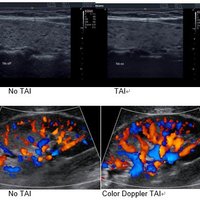

• Tissue Adaptive Imaging (TAI) kontinuierlich und automatisch optimiert die Bildgebung, um mehr Fokus auf den Patienten zu ermöglichen

• B-Modus: TAI fein stimmt mehrere Parameter für optimale Bildgebung ab

• Doppler: TAI passt sich dem Durchflusszustand an Verbesserte Kontinuität, Grenzerkennung und Ausfüllen